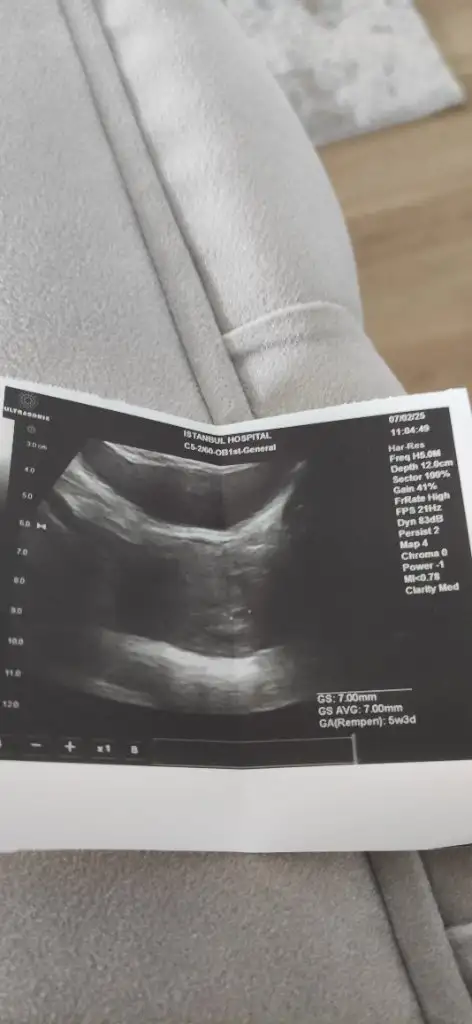

Ben 5+6 da gittim özel hastanede 3 mm ölçüldü sadece sonra devlete gittim 7 mm sizin ki de normal ultrason cihazı çok etkiliyor sonucuKese gören arkadaşlar gördüğü haftayı ve kese ölçüsünü yazabilir mi. 6+0 benim bugün ama 0,6 cm çıktı ikisi de. Evham yaptım az.

Maşallah canım alttanmi muayene ettiKizlar minik kuzumun kesesini gördük cok sukur bi maşallah alirizLioo canim keseyi ekleyebilirmisin tabloya 5+3 kalp atişi için 2 hafta sonra gel dedi

Benim sat 4 Ocak. Kese için 14 şubatta çağırdı kalbi duymayız ama kese görünür dediMerhaba, benim sat:3 ocaktı